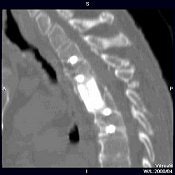

CT also can aid in finessing corpectomy procedures done to treat burst fractures. El-Khoury described an emergency case in which imaging saved the patient from further disaster (images A-F below).

"This patient arrived at the ER paraplegic. We see a little compression here, but we cannot see the entire problem. When we do CT, we see that this is a huge burst fracture. This was fairly acute. (The surgeon) did a corpectomy, which we followed with CT. He put a graft, two levels above and below the fusion," El-Khoury said. "When we looked closely at the CT, we noticed that the lower two screws are sitting and indenting the aorta. We called the surgeon and told him this: 'You have a situation in which you have metal screws pulsating against an aorta, and you know who is going to win in the end.' So the surgeon did an angiogram. The surgeon went in, removed the screws, and fused the patient from the back."